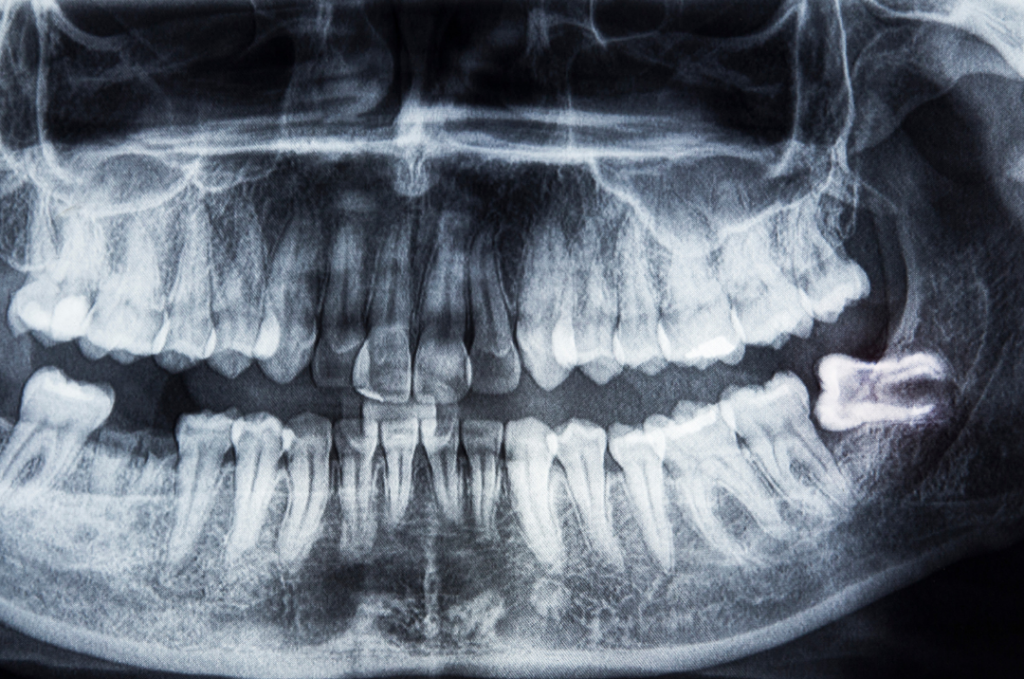

Digital dental X-ray showing an impacted wisdom tooth pushing against neighboring molars at Manassra Dental.

When it’s time to address those back molars, you want to be in the hands of Bay Area dental specialists who see you as a person, not just a procedure. At Manassra Dental, we use advanced diagnostic tools to see exactly how your wisdom teeth are growing. Sometimes these teeth grow in “impacted,” meaning they are stuck under the gum or pushing against your other teeth. By catching this early, we can perform a precise extraction that prevents damage to your healthy, straight teeth.

The best way to handle wisdom teeth is to monitor them before they hurt. During your regular oral exams near me, we use digital imaging to track the development of your third molars. Many patients don’t realize that wisdom teeth can cause cysts or gum disease long before you feel a single ache. By keeping up with your checkups at Manassra Dental, we can plan the best time for removal, usually in the late teens or early twenties when the roots haven’t fully “locked” into the bone yet.